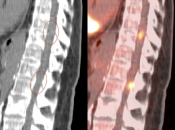

- Necrosis is typically non-avid on PET images.

- Recurrent malignancy will demonstrate FDG uptake, often focal and involving only a small portion of a surgical cavity. The uptake may be intense (an easy diagnosis) or may be minimally above adjacent background uptake (a more difficult diagnosis, which may require follow-up).

- FDG-avid recurrence should correspond to the area of enhancement noted on MRI (MRI should be done first, with images available at time of PET/CT interpretation).

- If no evidence of pathologic uptake, we report, “There is no evidence of high-grade tumor recurrence.”